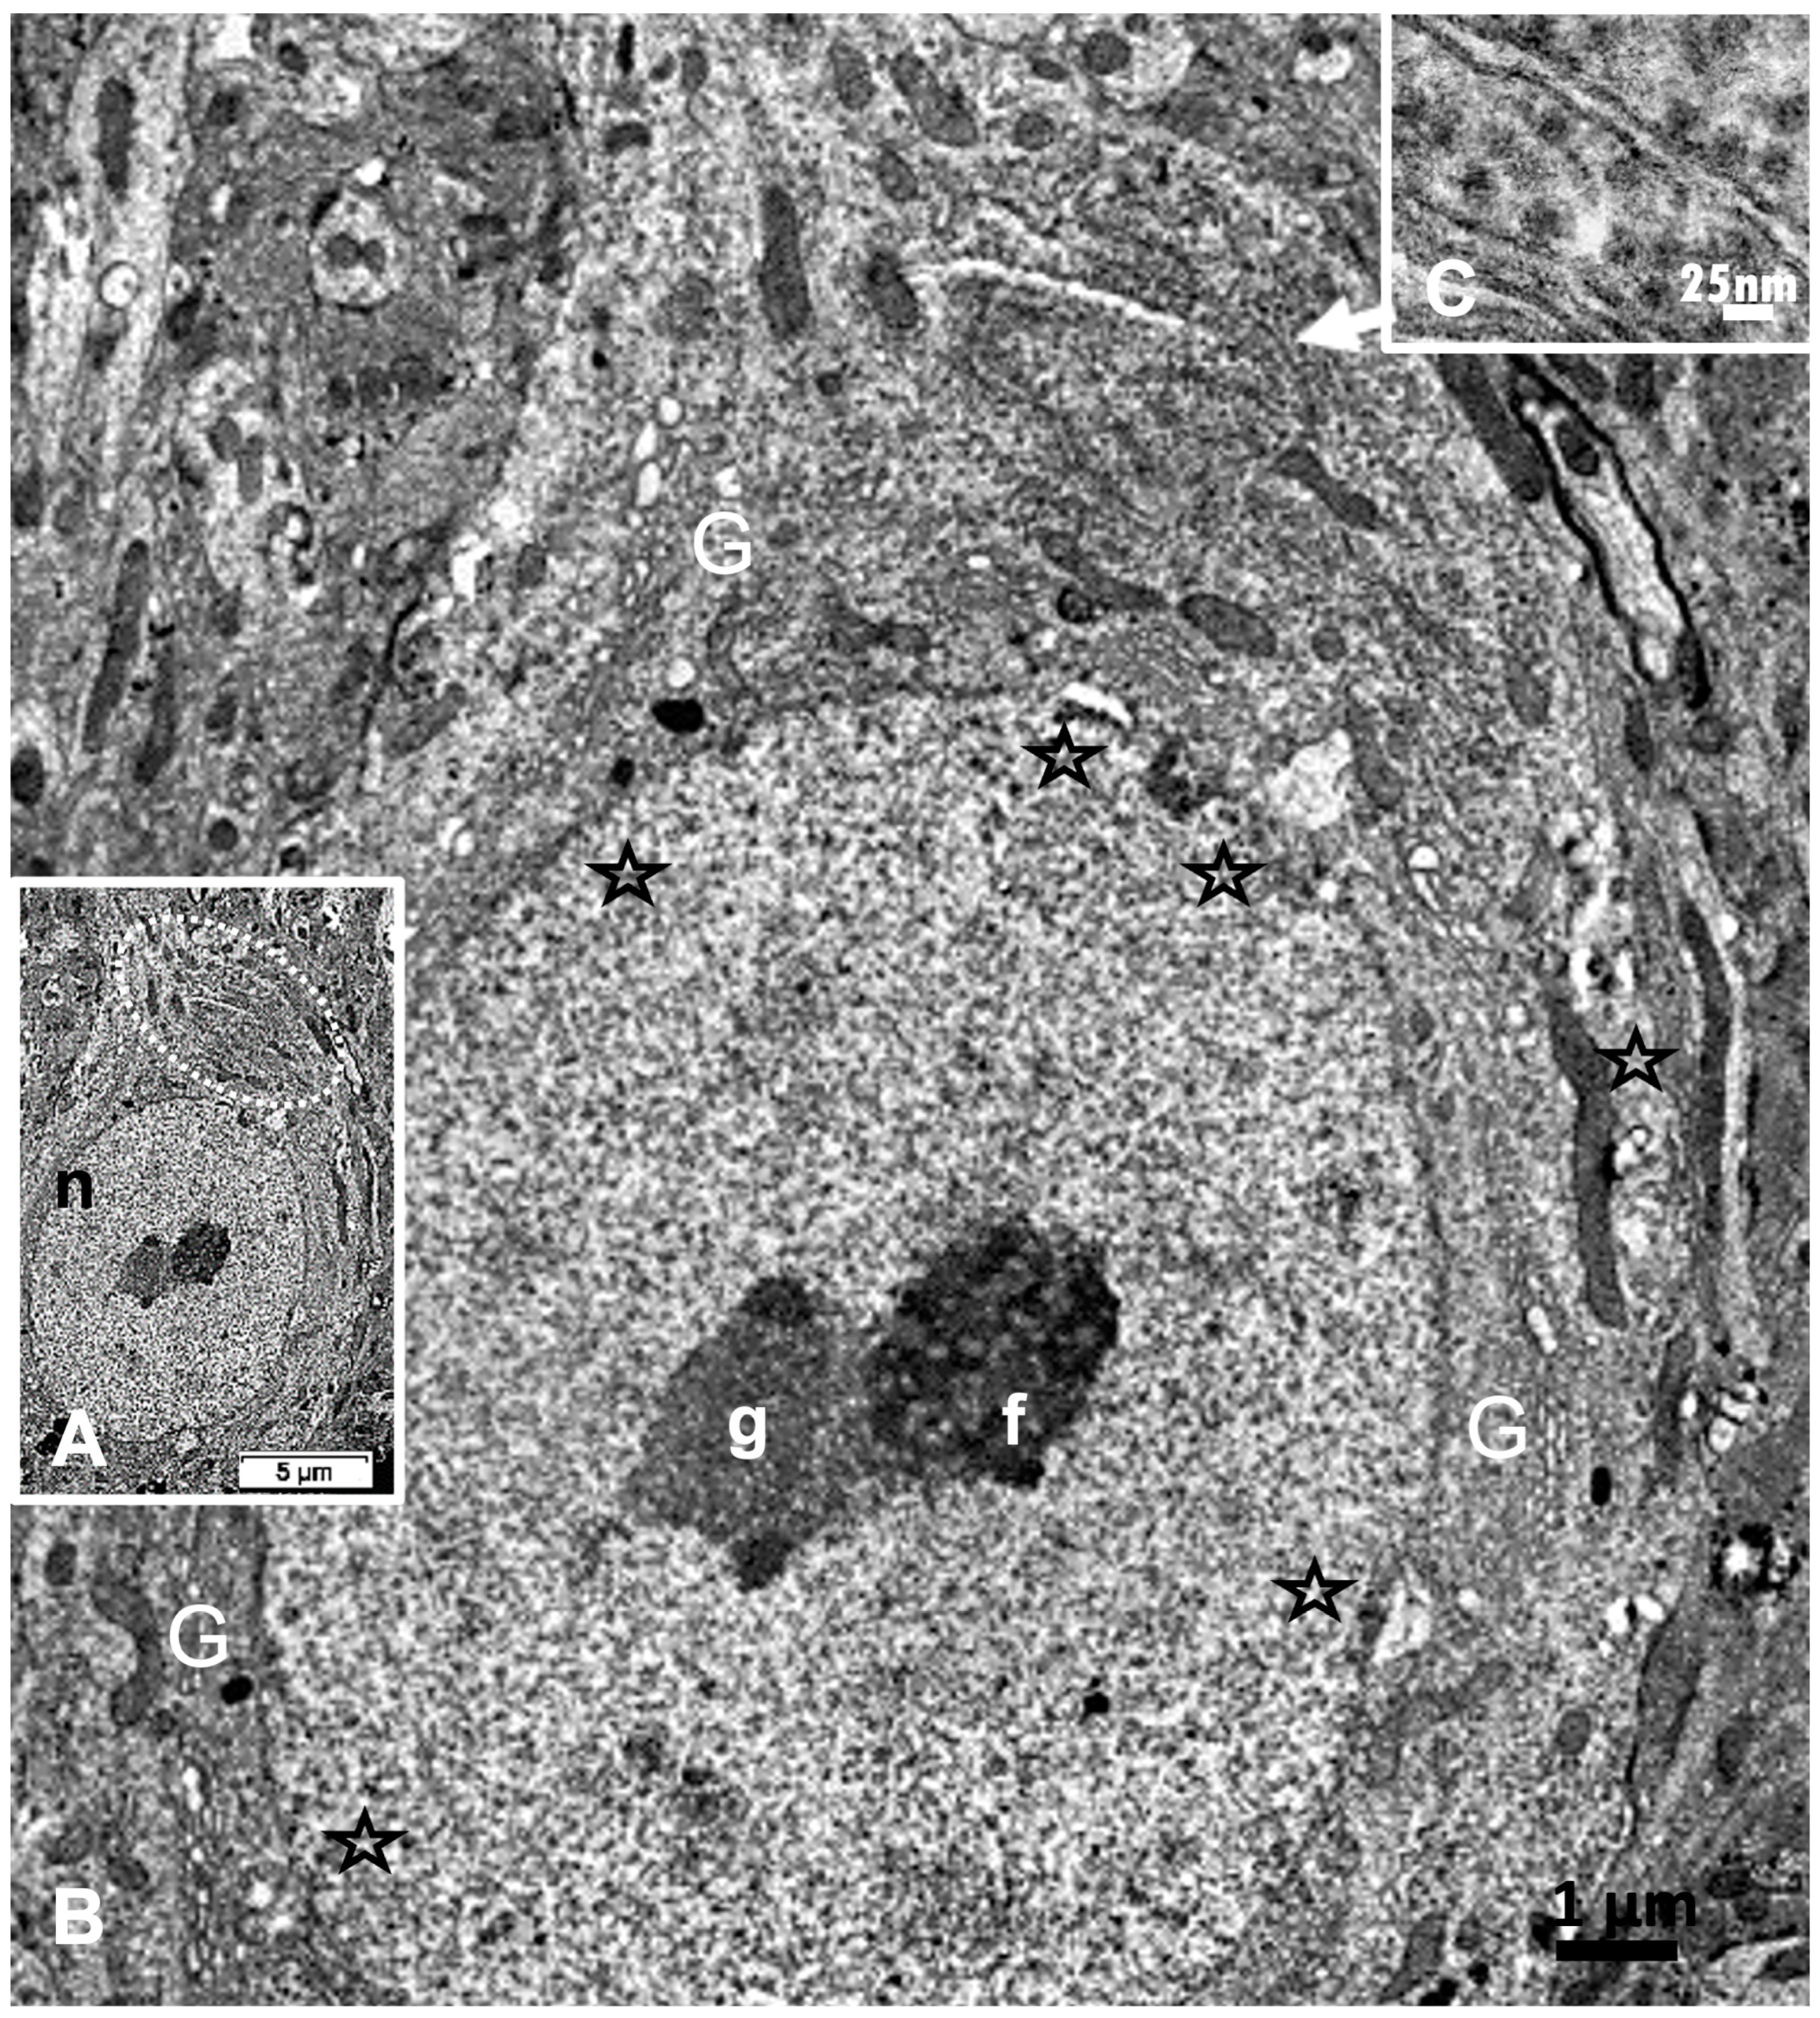

2.5. ARL13B Label in ODS48h: LM and TEM: A Primary Cilium Emergence

The thalamic neurons located adjacent but at less than 100 µm distal from the necrotic core ODS, as seen in Figure 8A–E, and more clearly in Figure 9, can be recognized from their shape, using LM, as a large pale nucleus with indent(s) that reveal an evident stained nucleolus and, with TEM, the same highly contrasted, large nucleolus shows large amounts of accumulated granular transcripts (as granular component) accompanying the dense and fine fibrillar components of the chromatin distributed throughout the very active nucleoplasm (Figure 9A, Figure 10A, Figure 11A and Figure A2). At first glimpse, the adjacent neuropil and the satellite oligodendrocytes appear typically located attached to neurons as satellites but, with TEM scrutiny, these were mostly damaged by ODS cell stress and are surrounded by large neuropil intercellular spaces throughout and possess other cells’ and myelin remnants, implicated after leakage of blood fluids, plasma with serum, contributed via the small regional necrotic cells to the archetypal term of ‘liquefaction necrosis’. However, within this ODS damaged zone outskirts, among some degraded and corpses of neuropil, resilient neurons found in the outskirt region were marked by large euchromatic nuclei and active nucleolus; they showed numerous ribonucleoproteins but also reveal through their fine structure that they possess delicate but clear-cut primary cilia (Figure 10A,B). Each cilium length ranged from 4.5 to 6.0 µm long and width from 0.2 to 0.25 µm that is filled with a core of granular cytoplasm and microtubules. The example illustrated shows its transition zone cell attachment consisting of a narrow transition segment or ‘neck’ of about 0.15 µm in width, that is tied by basal fibrillar materials, and forms a ciliary pocket or cove-like space of the plasma membrane. Within the neuroplasm, obscured by numerous ribosomes, a microtubule fascicle and other subcellular filaments can be barely seen originating from the adjacent perikaryal region and reaching the basal side of the primary cilium whose random sections constitute a sort of ‘hub’ region, probably endowed by a centriolar piece structure in some other ultrathin section. In Figure 10A–C, adjacent to the primary cilium, one can note filopodia-like extensions, as these could also be relevant to this rejuvenated change associated with cell resilience (Figure 10C). Other neurons of the same region (Figure 8D,E), at low magnification, bear an axon hillock that becomes like a funnel, similar to the neurons, and more distally located away from the core ODS damages, as shown in Figure 11, Figure 12, Figure 13, Figure 14 and Figure A2, displaying axon hillocks and an axon initial segment without any ciliation. Underlined by ocher yellow (Figure 12A) and enlarged in Figure 12B, the Golgi apparatus saccules characteristically erupt in numerous small vesicles (50–70 nm diam) that accompany ribonucleoprotein particles (mainly RNAs), revealing swirled ribbons of polysomes in places. Vesicles and particles appear to redistribute into the AIS, showing as an initial squeezed cylindric shape aligning the entered neurotubules into a paraxial to parallel orientation congested by one or more long, twisted mitochondrion. Both mitochondria profiles and inner neurolemma leaflet can be decorated by small round to elongated vesicles while the outer leaflet has typically no myelin. However, some synaptic contacts are noted amongst end-feet profiles of astrocytes, recognized by their highly contrasted granules of glycogen content (Figure 12A,B).

The LM yellow–ochre hue aspects of the ARL13B immunolabeled thalamic tissues appear as if covered with an overall from which scattered hole-like, oval to round shapes appear as ‘holes in the fabric’, where the nerve cell bodies, either isolated or as joined pairs or triplets exhibit poor contrast, as shown before with resilient nerve cells [66]; meanwhile, they maintain low resistance contact junctions with each other, as noted in Figure 12A [69]. However, the nuclei, poorly stained, disclose orthochromasy where contrasted nucleoli in pale blue staining according to hemalum reveal accumulated RNA transcripts with a chromatin DNA-stained dark blue hue [155,156]. Similarly, the semi-thin epoxy sections, prepared to choose zones to be ultra-cut, stained by toluidine blue, allow us to verify the abundant transcripts located in an appendix-like zonation with profused ribonucleoproteins [157,158]. Here, the axon hillock extends into the ARL13B labeled segment that is similarly richly endowed by transcripts, detected where the primary cilium and a future AIS grew after ODS, away from the demyelinated ODS epicenter, in the outskirts of the demyelinated thalamic zone. The resilient neurons show a perikaryal zone where most of the cells typical organelles and inclusions are located, including the Nissl bodies, contained cytoskeletal components among sparse polyribonucleoproteins associated or not with the endoplasmic reticulum along with mitochondria and apparently haphazardly oriented neurotubules (also known as microtubules) that are ultimately associated with the changing funnel shape of the cell extension that then possess these neurotubules, associated with neurofilaments and free ribosomes [159]. These neurocytologic components can also be viewed in our resilient neurons illustrated in Figure 7, Figure 8E, Figure 10, Figure 11, and Figure A2 where AIS is forming, as further explained in [159], with the earliest ultrastructural publications. There, according to the ODS lapse of time views, the typical perikaryal neuroplasm showed amassed polyribonucleoproteins (polysomes) within a distal region that yielded a sort of exocyst extended into a comma-shaped and in distal ODS into more or less long cylindrical extensions marked by an ARL13B label. It is after scrutiny of the ultrathin sections of these resilient neurons that a few of these sections (1 out of 15) revealed a display of a primary cilium (Figure 10A,B). These unique observations among ODS CNS damages confirmed those ARL13B labelings, similarly to those revealed for some oligodendrocytes within the same murine ODS damage region [68]. The occurrence of such neuronal primary cilium outgrowth was not investigated elsewhere in the CNS; one of the reasons is that, unlike the thalamic nuclei, the centropontine regions or subcortical regions are inconsistently affected by demyelinating lesions in the model of ODS in mice [62].

This primary cilium cell appendage was observed and described a long time ago [160], including with high morphologic resolution by electron microscope tomography [161]; its physiologic sensing functions have only been recently investigated in numerous normal and pathology cells and tissues as found in all embryonically derived epithelial cells from in vitro and in vivo studies, where this appendage was found to be a mechanical, flow sensing device but also as osmosensor [162,163,164,165]. Its dysgenesis and mutations of the cilium-associated structure and membrane signaling proteins favor insensitivity and growth anomalies such as polycystic kidney disease (PKD), Bardet–Biedl syndrome (BBS) and/or other cranio-facial dysgenesis as a modulator function of tissue’s differentiation [166,167,168,169,170]. In the CNS, the primary cilium appeared crucial in adequate morphogenesis as it was involved in correct neurogenesis in cortical development as well as for axon growth [166,167,168,170,171,172,173,174,175,176,177,178,179,180,181].

Accordingly, the primary cilium phenotype in mature CNS can indicate some revitalized nervous structures and be a marked precursor for other noted repairs [66,68] that confirmed a complex cascade of transduction signals triggered by morphogen growth factors or electric stimuli. As an example, secreted smoothened hedgehog (Shh), a protein signaling bound patch (Ptc) at the cell surface, relieved inhibition of a transmembrane protein, smoothened (Smo), that can further conduct a cascade of transduction activations in the arf family genes that are included the ARL13B expression and are labelled as such in our CNS tissues [68,176,177,178,179]. Ultimately, these emerged cilium and associated filopodia (Figure 11C) structures verified that some restored axon extension would progress as an axon hillock region into a rebuilt AIS and the distal axon segments. Meanwhile, as a side note, it emerged out of these resilient nerve cell bodies filopodia that accompany the primary cilium signal sensor appendage that other mechanosensors should become ablated by endocytosis while further growth and differentiation occurred [180,181] into matured circuitry, involving the AIS and the distal axon interconnections [182,183,184] as influenced by soma location and morphology [185].